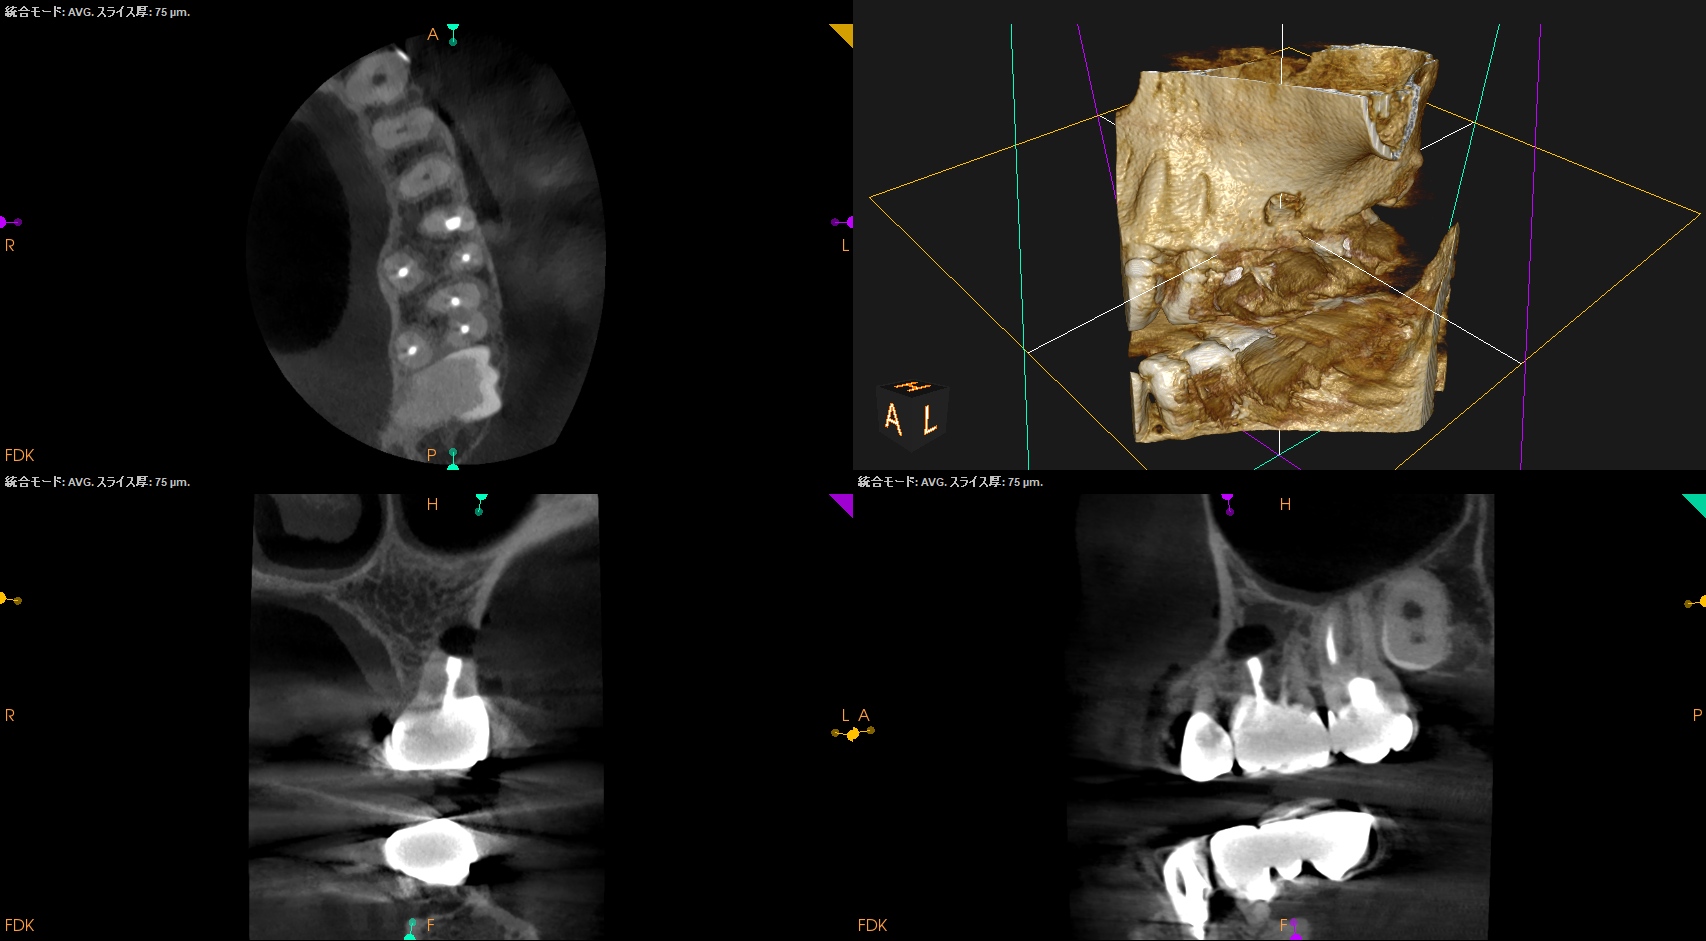

#14 MB Apicoectomy(2025.3.31)

ペリオプローブを使用し、MBのApexを類推した。

OsteotomyしApexから3mmで切断した。

その後メチレンブルーで染色し、CBCTの絵と相似になっていることを確かめて逆根管形成した。

Lid techniqueで逆根管充填した。

術後にPA, CBCTを撮影した。

最後に縫合して終了した。